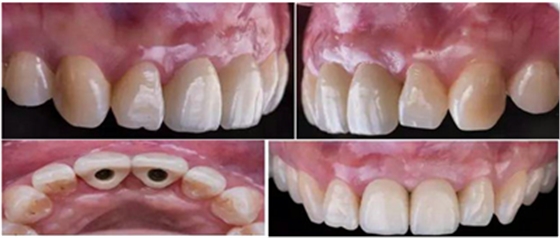

治療效果

修復(fù)前

修復(fù)后

本病例中通過(guò)對(duì)患者修復(fù)體佩戴后的舌側(cè)、頰側(cè)、左側(cè)、右側(cè)以及微笑照的采集,充分展示修復(fù)體在口內(nèi)的佩戴情況,可以看到無(wú)論顏色還是與鄰牙的匹配適宜度都是非常高,也比較吻合年輕女性對(duì)美觀的要求。同時(shí),通過(guò)術(shù)后多次隨訪及跟蹤患者后期使用狀況,患者也對(duì)修復(fù)效果十分滿意。